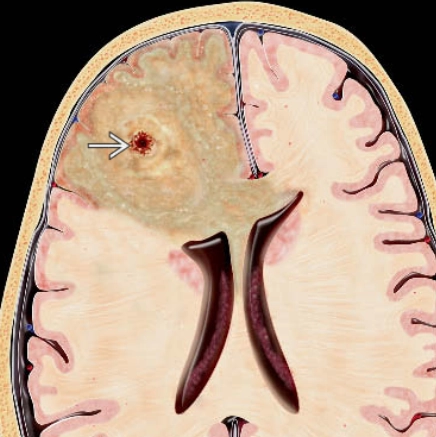

Di căn nhu mô não (Parenchymal metastases)